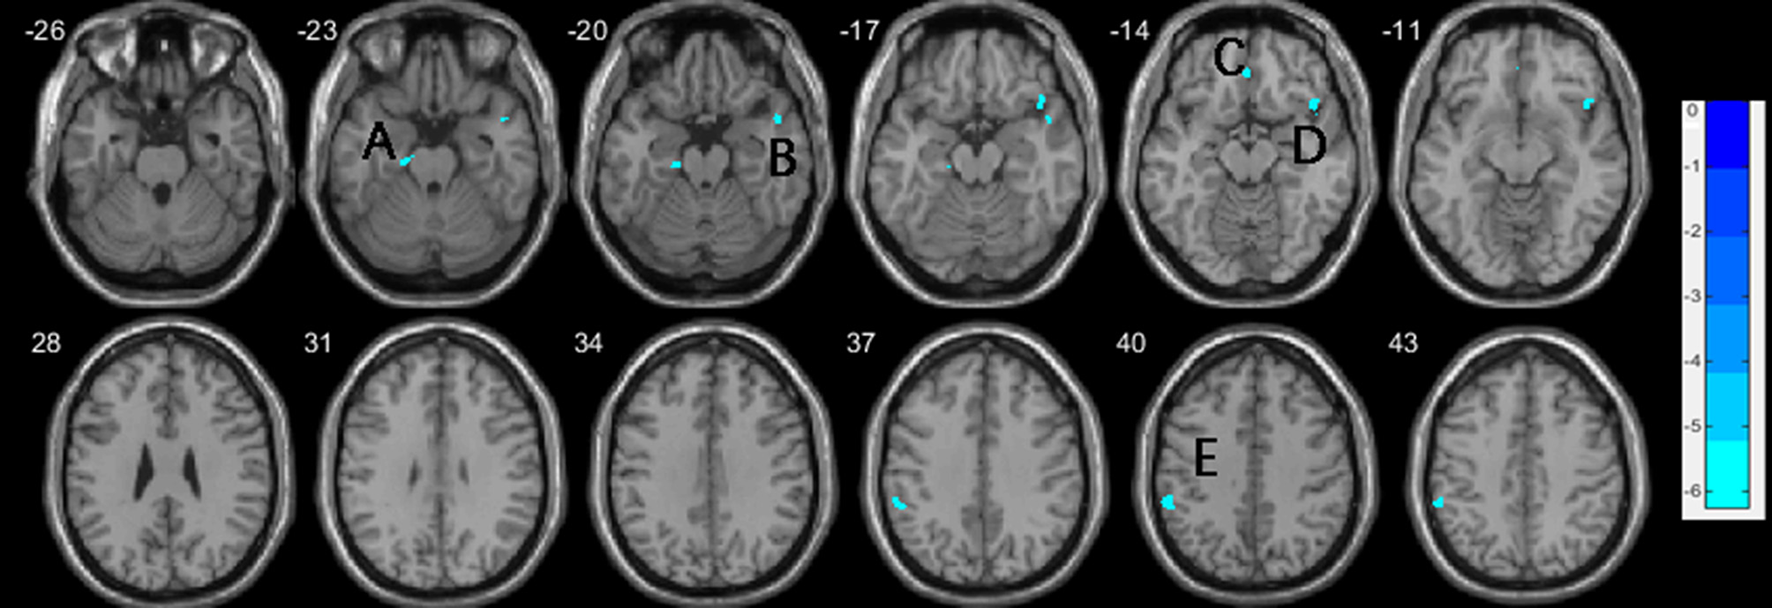

One-way ANCOVA (P < 0.001, uncorrected) revealed significant differences in GMV in widespread regions, including the right superior temporal gyrus (STG), right insula gyrus (INS), right temporal pole (superior and middle temporal gyrus [TP]), left fusiform gyrus (FFG), left parahippocampal gyrus (PHG), bilateral medial orbital frontal gyri (mOFG), bilateral orbital inferior frontal gyri (IFGorb) and left inferior parietal lobe (IPL), between the three groups. Post-hoc t-test showed that, compared to HCs, vSZ showed significantly reduced GMV in a large cluster from the right STG to the insula (INS), TP, and IFGorb. Other regions showing reduced GMV in the vSZ group were the left FFG, IFGorb, and right opercular IFG (IFGoper) (P < 0.05, FWE corrected; Table 2; Figures 1, 3). In the nvSZ group, reduced GMV was found in the left IPL, PHG, the bilateral mOFG, and the right superior TP and IFGorb, as compared to the HC group (P < 0.05, FWE corrected; Table 2; Figures 2, 3). Marked decrease was found in the GMV of the right temporal lobe and bilateral IFG in the vSZ group rather than the nvSZ group, as compared with HCs. In addition, a more pronounced decline of GMV in the left IPL was found in the nvSZ group as compared to the vSZ group, although there was no significant difference. The results obtained by using TFCE were quite similar with our original results (see Supplementary Table 1; Supplementary Figures 1–3).

Figure 2

Decreases of gray matter volume in the nvSZ group compared to HCs, with age, education, and TIV controlled. (A) left parahippocam

pal gyrus; (B) right temporal Pole: superior temporal gyrus; (C) right rectus, extending to bilateral medial orbital frontal gyrus; (D) right inferior frontal gyrus, orbital; (E) left inferior parietal lobe. TIV, total intracranial volume.